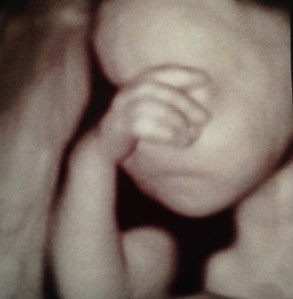

(and yes, these are actual 3D ultrasound pictures of Ella – she looks great already!)

What incredible images! She’s so beautiful :-)